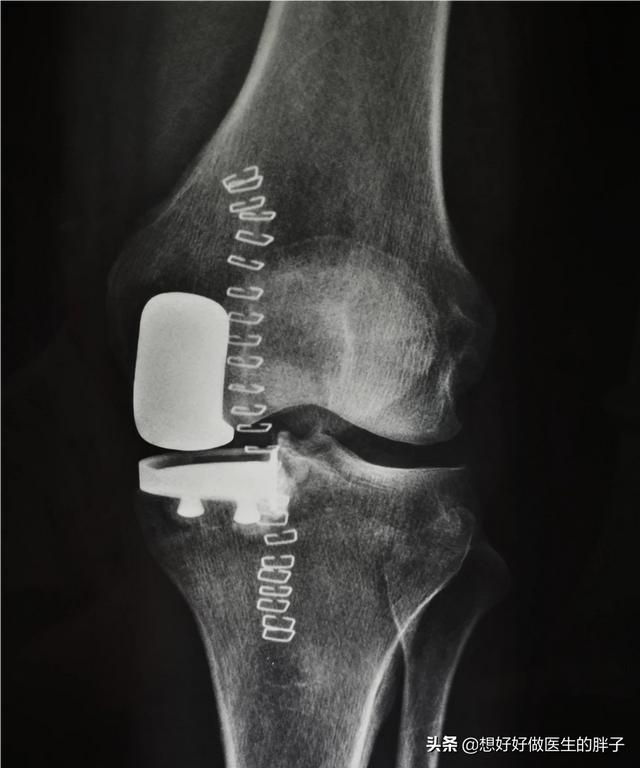

stade avancé de la maladiequi se manifeste généralement par des douleurs plus intenses au niveau du genou, certains patients présentant des déficits importants de flexion et d'extension de l'articulation, lorsque l'affection est suffisamment grave pour se manifester.Douleurs au repos et douleurs nocturnesC'est le signe que l'état du patient a atteint un point tel qu'une intervention chirurgicale est nécessaire pour le résoudre. Ce type de chirurgie est appeléremplacement du genouDe nombreuses personnes pensent que l'ensemble de l'os de l'articulation du genou est retiré et remplacé par une prothèse. Cette compréhension est erronée, la chirurgie de remplacement du genou consiste à retirer la surface cartilagineuse cassée et à la remplacer par une surface métallique, c'est pourquoi elle est également appelée chirurgie de remplacement de la surface de l'articulation du genou. Avec les progrès de la technologie actuelle, afin de protéger et de préserver davantage l'articulation du patient, on commence également à pratiquer des opérations de remplacement de la surface de l'articulation du genou.arthroplastie partielle。

Lorsque les patients subissent un traitement chirurgical pour une prothèse articulaire, un bon exercice de rééducation systématique permet d'obtenir de très bons résultats postopératoires.